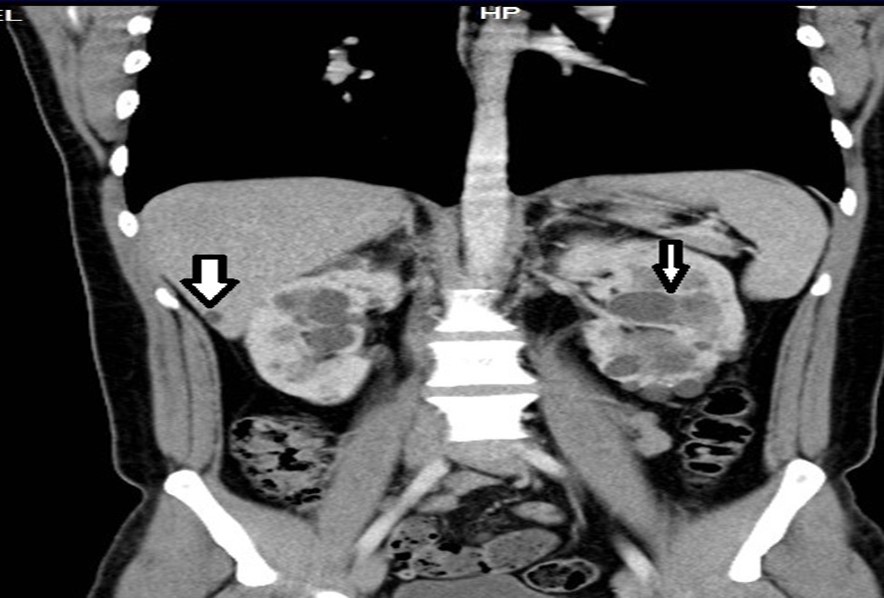

33-year-old male, son of the woman from case 1, with diagnosis of polycystic kidney and liver disease (Figure 3, Figure 4) since 29 years old , with normal liver and kidney function; At that moment general measures were started based on a diet low in sodium, increasing the consumption of natural liquids, avoiding nephrotoxic drugs and monitoring blood pressure.

At physical examination, without alterations. The abdominal thomography reports kidneys in habitual anatomical projection with loss of their morphology and increased sizes with loss of the sinus parenchyma relationship due to cystic-looking structures; right kidney with dimensions 14.3x 8.9 x 6.6 cm left kidney 17.3 x 11.6 x 8.2 cm in its longitudinal, transverse and anteroposterior diameters respectively, poorly determined echogenic renal sinuses, the left renal sinus with solid oval shades measuring 0.6 to 0.8cm on average and some calcifications; liver ultrasound showed cystic lesions. Laboratory creatinine 0.96mg/dl, urea 31.03 mg/dl

Figure 3.Contrast CT coronal reconstruction shows small liver cysts, kidneys are enlarged by multiple cysts.